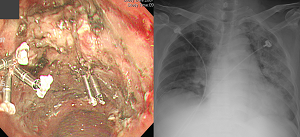

Àú´Â 20³â °¡±îÀÌ ESD¸¦ Çϰí ÀÖÁö¸¸ phlegmonous gastritis´Â ¼ö ³â Àü¿¡ µü ÇÑ ¹ø °æÇèÇÏ¿´½À´Ï´Ù (¾Æ·¡ »çÁø).

ȯÀÚ°¡ ±¸¸¦ Á¤µµ·Î ¾ÆÆÄÇϰí, ÁøÅëÁ¦¿Í Ç×»ýÁ¦¸¦ ½áµµ ¸î ½Ã°£ µ¿¾È °¡¶ó¾ÉÁö ¾Ê¾Æ¼ total gastrectomy¸¦ °í·ÁÇß½À´Ï´Ù. µü 6½Ã°£¸¸ ±â´Ù·Á º» ÈÄ ¼ö¼úÀ» ÃÖÁ¾ °áÁ¤ÇÏÀÚ°í ȯÀÚ¿Í »óÀÇÇÑ ÈÄ ±â´Ù·È´Âµ¥ ´ÙÇེ·´°Ôµµ Á¶±Ý¾¿ Á¶±Ý¾¿ ÁÁ¾ÆÁ³°í °á±¹ ¼ö¼úÇÏÁö ¾Ê°í Åð¿øÇÒ ¼ö ÀÖ¾ú½À´Ï´Ù. ¿øÀÎÀº ¾ÆÁ÷µµ ¸ð¸£°Ú½À´Ï´Ù. [2015-12-8. ÀÌÁØÇà]